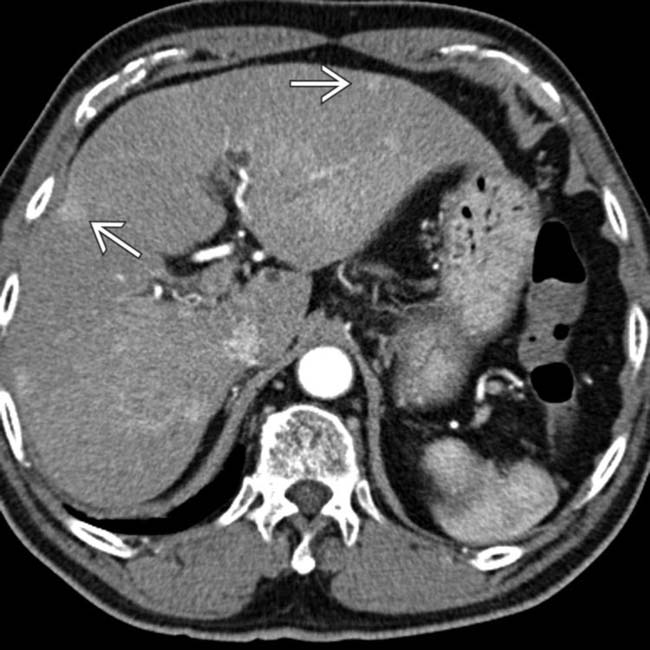

Congenital intrahepatic portosystemic venous shunt and liver mass in What Is A Shunt For Liver Transjugular intrahepatic portosystemic shunt (tips) a tips relieves the high blood pressure in the portal vein (called portal hypertension) that often occurs in the setting of liver. This vein is responsible for carrying blood from your abdomen to your liver. A liver shunt is an unnatural connection that develops between the portal vein and systemic veins. Transjugular intrahepatic portosystemic shunt. What Is A Shunt For Liver.